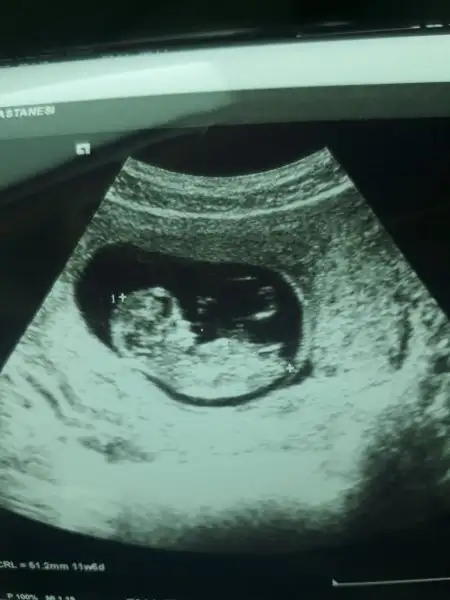

Ilk cocuk mu.Valla açıkcası fiyatları uygun olsaydı biraz eve bile ultrason cihazı almak için baktık eşimle :)) ama 30 binleri buluyormuş o yüzden vazgeçtik tabi :) benim özeldeki randevum 5 Temmuz'da devletteki randevum 28 Haziran duramıyorum bende evdeyim çalışmıyorum da zaman geçmiyor surekli düşünmekten

Goster bize yine insallah bebisi evet her doktor kontrolunu beklemek cile o gun geldigindeyse korku heyecan karisik duygular ❤ seninle ayniyiz ben de sali gidicem ikili test icin uygun olursa onu yaptircam bakalim ❤Insallah kizlar korku heyecan karisik.. 2 de randevum.. yazarim size